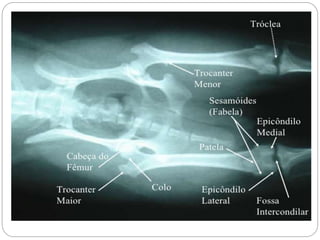

Trocanter menor Cabeça do fêmur Troncater maior Côndilo medial Fossaintercondilar Côndilo lateral Fêmur de cão, vista caudal Fêmur de cão, vista cranial Trocanter maiorcabeça Ttocante menor Epicôndilo lateral Epicôndilo medial Tróclea